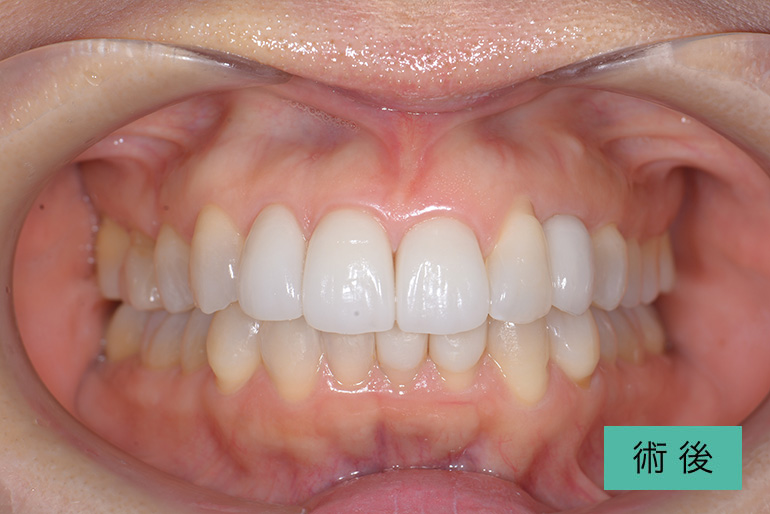

オールセラミック②

| 治療内容 | 上顎前歯右上3番から左上3番のセラミック冠 |

|---|---|

| 治療期間・回数 | 約1ヶ月、3回 |

| 費用(税込) | ¥990,000(165,000/1本)(補綴費用) ※自由診療 |

| リスク・副作用 | 疼痛、補綴物の脱落、咬合違和感、破折 |